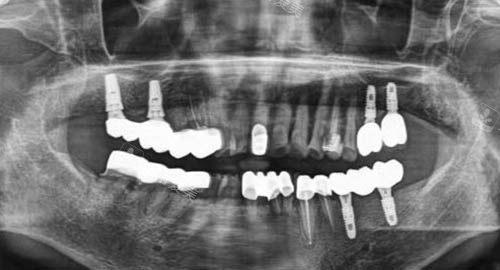

多颗牙齿种植ct

牙齿种植牙模型卡通示意图

牙齿种植卡通示意图